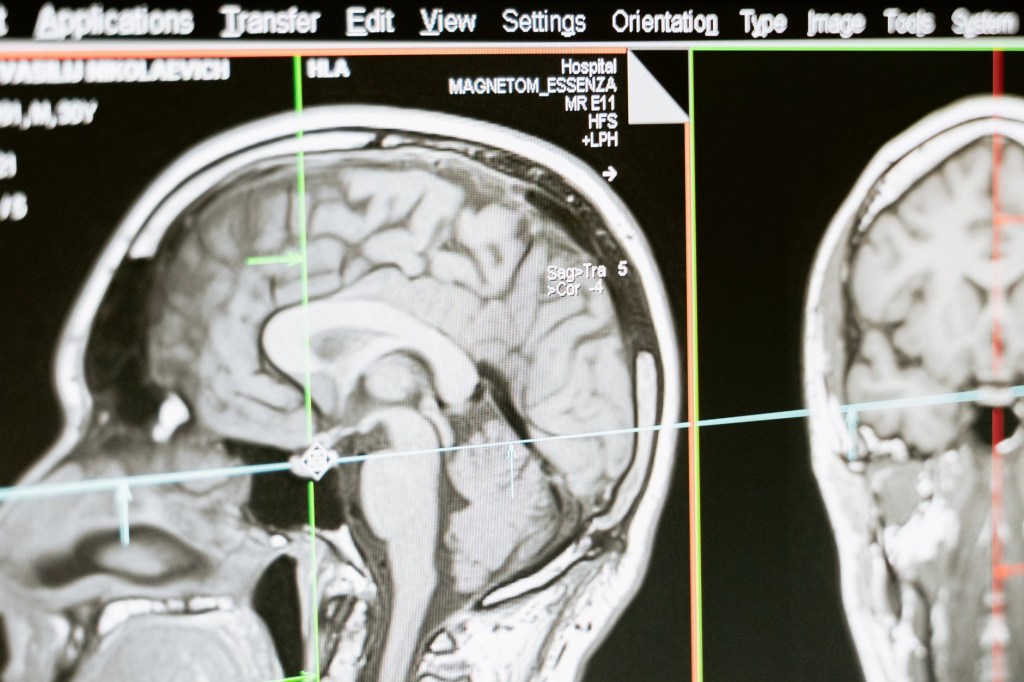

COVID-19 infection affects brain and mental health

A recent paper published in Lancet Psychiatry reports that at least 1 in 3 patients , who have recovered from severe COVID, have substantial neurological and psychiatric problems during the next six months .